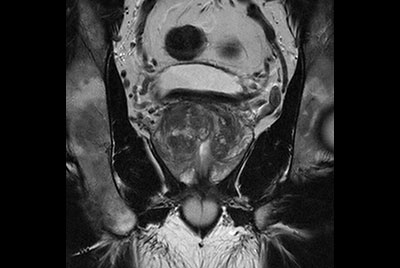

Prostate with dual coil set-up